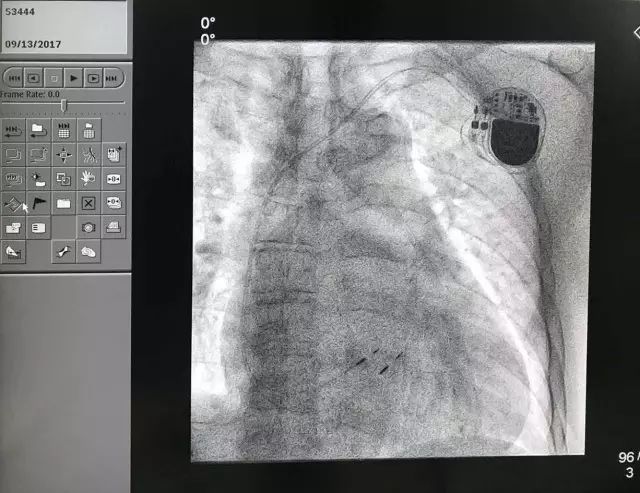

患者是一名79岁的男性病人,长程持续性房颤伴二度房室阻滞,平均室率52bpm,双房巨大,而且右心衰,双下肢浮肿、消瘦。

因为心动过缓,患者需要心室起搏支持,而常规心室起搏破坏心室收缩同步性,会令原本存在的心衰加重,因此考虑施行希氏束起搏,以达到最佳的生理性起搏。

手术大约2小时,过程非常顺利,获得希氏束起搏阈值0.75V/0.5ms。心室后备起搏参数0.5V/0.5ms。事实证明,希氏束起搏和之前预测的一样,达到了非常理想、而且是疗效最佳的结果。